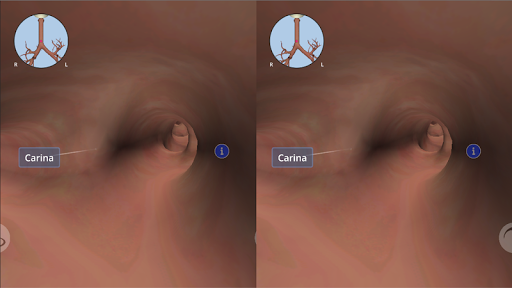

باستخدام الواقع الافتراضي ، سوف تكون قادرًا على التنقل على طول الهياكل التشريحية ، لتصبح جزءًا من علم التشريح البشري: الجهاز الدوري ، والجهاز التنفسي ، والجهاز الهضمي ، والبولي ، الدموي ، والإناث.

يمكن استخدام Anatomyou VR في وضعين مختلفين: الواقع الافتراضي وملء الشاشة.

في وضع الواقع الافتراضي ، يجب إدراج الجهاز المحمول (الهاتف الذكي) في أداة الواقع الافتراضي للاستمتاع بتجربة غامرة بالكامل. يمكن للمستخدم التفاعل مع عناصر التحكم في التنقل وعناصر المعلومات التشريحية من خلال توجيهها.

على الرغم من أنه يوفر أفضل تجربة عند استخدامه في وضع الواقع الافتراضي ، إلا أنه يمكن للمستخدم الاستمتاع والتعلم مع تطبيق الهاتف المحمول هذا في وضع ملء الشاشة ، دون الحاجة إلى أداة الواقع الافتراضي.